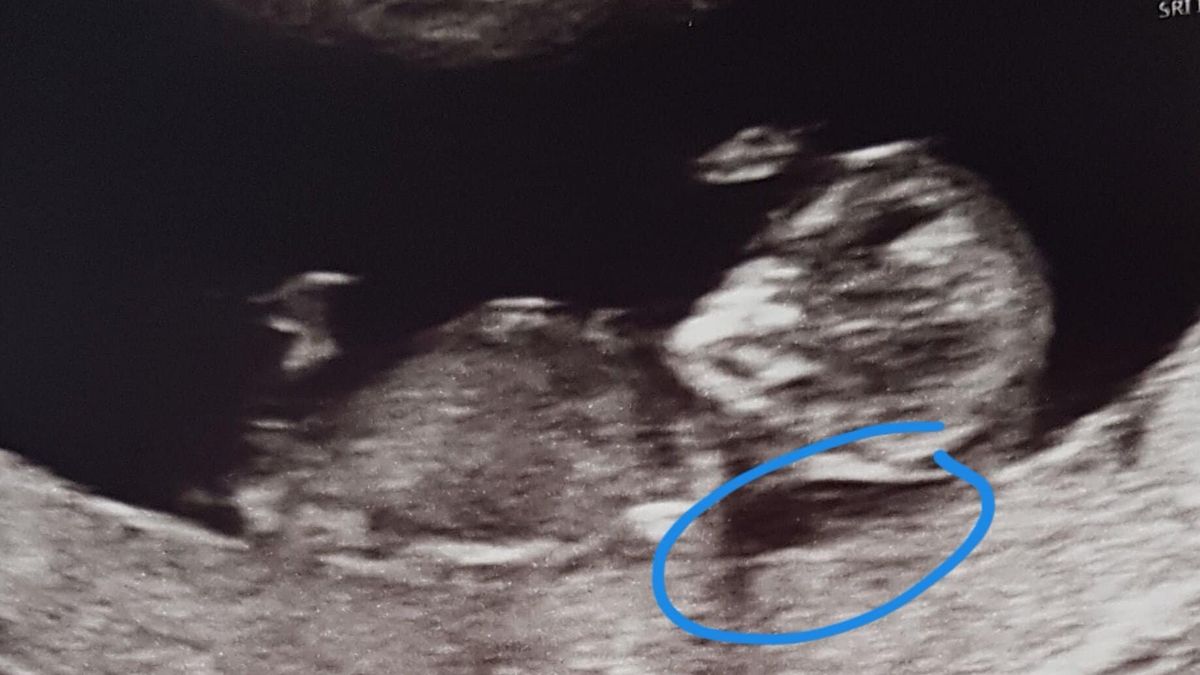

A las 10 semanas otra ecografía, la llamada prueba de datación. Esto se hizo dos veces en nuestro hospital. A las 8 y a las 10 semanas. Fuimos a la partera sin ninguna preocupación. El latido del corazón era fuerte. Teníamos curiosidad por ver si la estimación de la fecha seguía siendo precisa. Dejamos a nuestro hijo mayor con los abuelos y fuimos rápidamente. En el hospital, las ecografías no las realizaba la partera. Primero ibas al departamento de ecografías y luego a tu cita con la partera o el obstetra. El latido del corazón era fuerte. Pero entonces la ecografista se volvió más silenciosa. Preguntó si queríamos echar un vistazo al cuello. Mostró la translucencia nucal. Era demasiado gruesa. Movió el ratón sobre la pantalla y midió el diámetro de la translucencia nucal. Registró el grosor. Luego preguntó si podía desvestirme. También quería hacer una ecografía transvaginal. En el probador, un sentimiento de miedo se apoderó de mí. Algo estaba mal. Su rostro se veía preocupado. Intentamos averiguar qué estaba mal. No dijo mucho. 'Las opciones se pueden discutir con la partera más tarde', dijo. 'Cuáles son los siguientes pasos, qué significa.' No entendíamos. A pesar de ser padres durante casi 3 años, no sabía que una translucencia nucal engrosada era una mala señal. Inmediatamente pensé en el síndrome de Down, pero nada más. La ecografista explicó que cualquier cosa por encima de 2.5 milímetros es demasiado gruesa. Estábamos en 3.5. No era una cantidad enorme, pero no era buena. Me vestí, temblando. Ella lo vio, nos dio un vaso de agua y fue a buscar a la partera. Nos llevó directamente a su habitación, sin una sala de espera abarrotada en la que sentarse. Se nos permitió pasar directamente. Se tomó todo el tiempo que necesitábamos. Preguntó qué queríamos. Queríamos hacernos el NIPT de todos modos, que no estaba disponible para todos con nuestro hijo mayor. La partera pensó que esto era prudente.

El eco es intenso

En la ecografía, puedes ver la aguja entrando en tu útero. Puedes ver que el bebé no está cerca. Hay un doctor para la inyección, un ecografista para la ecografía y una enfermera de apoyo. Es muy reconfortante tener a tantas personas cuidándote. Mi esposo está allí, y después, nos extraen sangre a ambos. Si encuentran algo, lo compararán con nuestra sangre. A veces es una 'anomalía' que uno de los padres también tiene, y entonces saben inmediatamente en qué medida es grave o no. Nos vamos a casa a esperar. La próxima ecografía es la siguiente semana. Va increíblemente bien. No ven nada preocupante, y la translucencia nucal finalmente ha asumido proporciones normales. Brindemos por más buenas noticias.